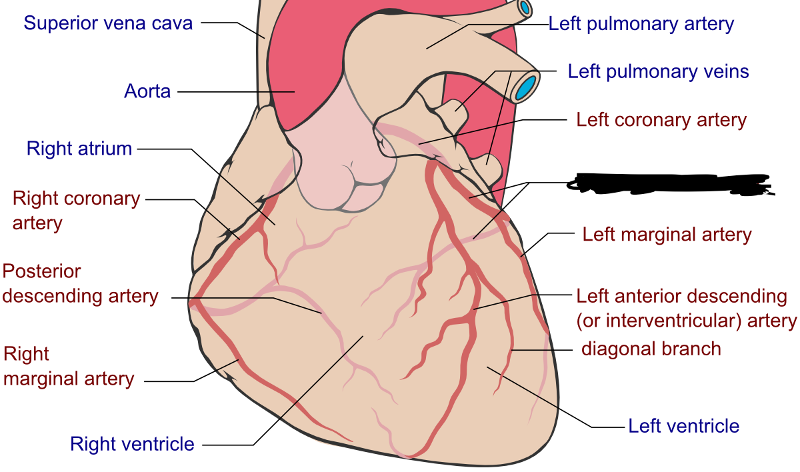

Anterior interventricular sulcus

Posterior interventricular sulcus

Circumflex branch (of the left coronary artery)

Coronary sinus

interventricular branch of the left coronary artery. = left anterior descending artery (LADA))

Left/right coronary artery

left/right pulmonary artery/vein

left/right ventricle

Pulmonary trunk

Pulmonary valve (=right semilunar)

Superior/inferior vena cava